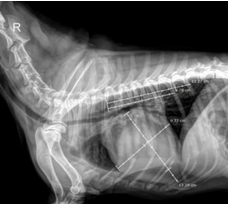

Fig. 2. Measurement of VHS in Dogs with MMVD

The results in Figure 2 show that imaging parameters changed markedly with disease progression. The vertebral heart scale (VHS) increased significantly from stage B1 to B2 and C (p < 0.001), reflecting cardiomegaly due to chronic volume overload. Mean VHS increased from 10.00 ± 0.19 (B1) to 10.85 ± 0.18 (B2) and 11.66 ± 0.32 (C), consistent with the findings of Levicar et al. (2022), who reported that VHS > 11 is an early indicator of congestive heart failure. The QUEST study and Häggström et al. (2008) also indicated that VHS > 10.5 is associated with poor prognosis.

Fig. 3. Measurement of the LA/Ao ratio in dogs with MMVD

The LA/Ao ratio increased significantly across stages (p < 0.001), from 1.38 ± 0.10 (B1) to 1.76 ± 0.08 (B2) and 2.18 ± 0.17 (C). According to the EPIC trial (Boswood et al., 2016), LA/Ao ≥ 1.6 defines stage B2. The high LA/Ao values in stage C reflect severe left atrial enlargement due to chronic mitral regurgitation and are closely associated with the risk of congestive heart failure and survival time (Boswood et al., 2016).

Table 3. Radiographic and echocardiographic parameters in dogs with MMVD at different ACVIM stages

| Stage | Statistical parameters | Indices | ||||

|---|---|---|---|---|---|---|

| VHS | LA/Ao | FS | LVIDd | LVIDs | ||

| B1 | n | 6 | 6 | 6 | 6 | 6 |

| Mean | 10.00c | 1.38c | 59.82c | 1.47c | 0.67c | |

| SD | 0.19 | 0.10 | 9.35 | 0.03 | 0.12 | |

| Min | 9.80 | 1.26 | 40.51 | 1.42 | 0.54 | |

| Max | 10.30 | 1.51 | 60.72 | 1.50 | 0.85 | |

| B2 | n | 55 | 55 | 55 | 55 | 55 |

| Mean | 10.85b | 1.76b | 52.03a | 1.75b | 0.81b | |

| SD | 0.18 | 0.08 | 9.47 | 0.03 | 0.10 | |

| Min | 10.60 | 1.62 | 37.26 | 1.70 | 0.65 | |

| Max | 11.20 | 1.91 | 80.35 | 1.84 | 0.99 | |

| C | n | 23 | 23 | 23 | 23 | 23 |

| Mean | 11.66a | 2.18a | 49.70a | 2.03a | 0.99a | |

| SD | 0.32 | 0.17 | 9.90 | 0.06 | 0.09 | |

| Min | 11.00 | 1.96 | 29.64 | 1.70 | 0.79 | |

| Max | 12.00 | 2.50 | 81.49 | 1.84 | 1.10 | |

| P – value | 0.000 | 0.000 | 0.575 | 0.000 | 0.000 | |

In contrast, fractional shortening (FS) decreased only slightly from 52.92% (B1) to 49.70% (C) and showed no significant difference (p = 0.575). This agrees the ACVIM consensus that MMVD mainly causes volume overload rather than primary systolic dysfunction; therefore, FS has limited value in assessing disease severity.

Both LVIDd and LVIDs increased significantly (p < 0.001) from B1 to C, indicating progressive eccentric hypertrophy and left ventricular remodelling. These findings are consistent with Franco et al. (2011), who showed that these indices are sensitive markers of disease progression and treatment response. Thus, imaging parameters, especially VHS, LA/Ao, and LVIDd/LVIDs, are highly valuable for staging and prognostication of MMVD. Thresholds such as VHS > 10.5–11, LA/Ao > 1.6–2.0, and LVIDd > 2.0 help distinguish compensated from decompensated stages. Although FS remains within normal limits in early stages, structural changes of the cardiac chambers occur early, indicating that assessment of cardiac morphology should be prioritized over systolic function alone in monitoring MMVD.